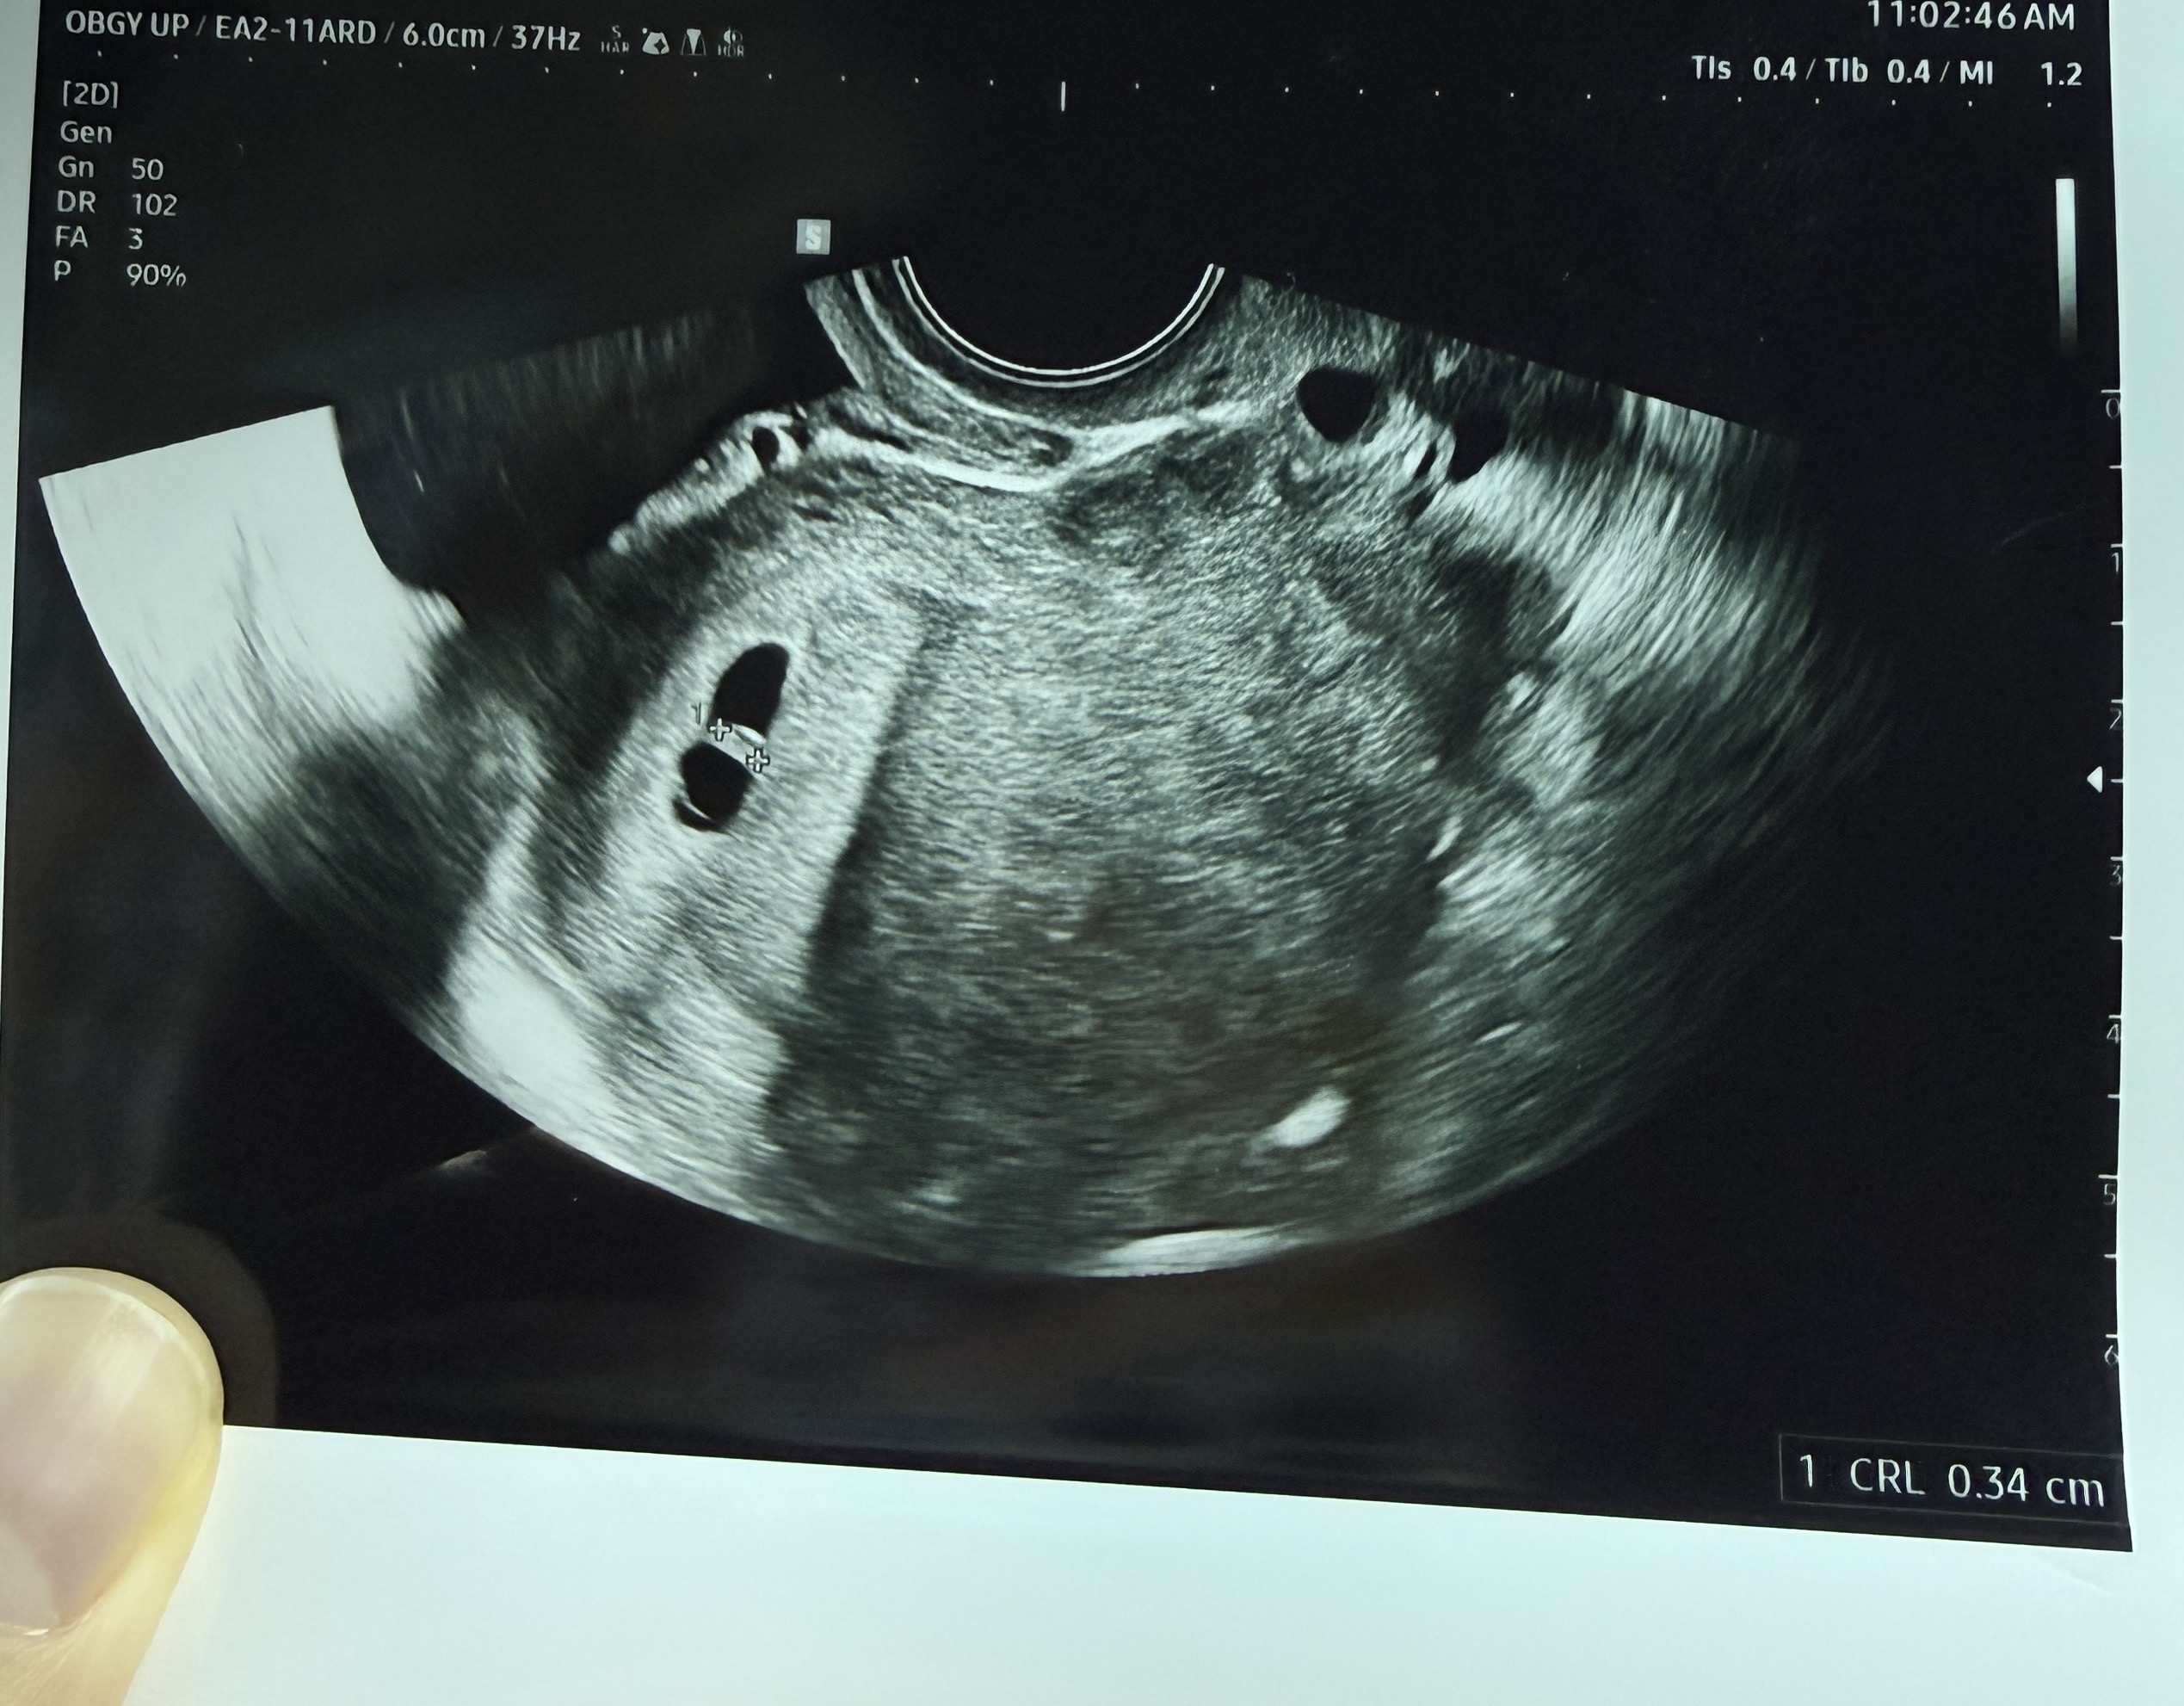

5주차3일에 아기집 확인하고 2주 뒤에 보자고 하셔서 진료 기다리던 와중에 오늘 아침 약간 갈색혈+사르르 배아픔에 오전에 급하게 병원에 다녀왔어요. 7주1일차 아기가 보통 5mm정도 되야하는데 오늘 가서 보니 3mm정도 더라구요. 심장소리도 아주 아주 약하고 의사샘은 들리지 않는다고 표현하셨어요. 아직 유산 판단은 이르고 일주일 뒤에 다시 보기로 했고, 7mm까지 클때까지 지켜본 뒤 심장소리나 그 외 약한 부분이 있을 때 결과가 날 것 같다고 하셨어요. 7주차에 심장소리 못듣고 8주차즈음 들으신 분 또는 이 즈음부터 아기가 정상 크기로 자라신 분 있는지 궁금해요.